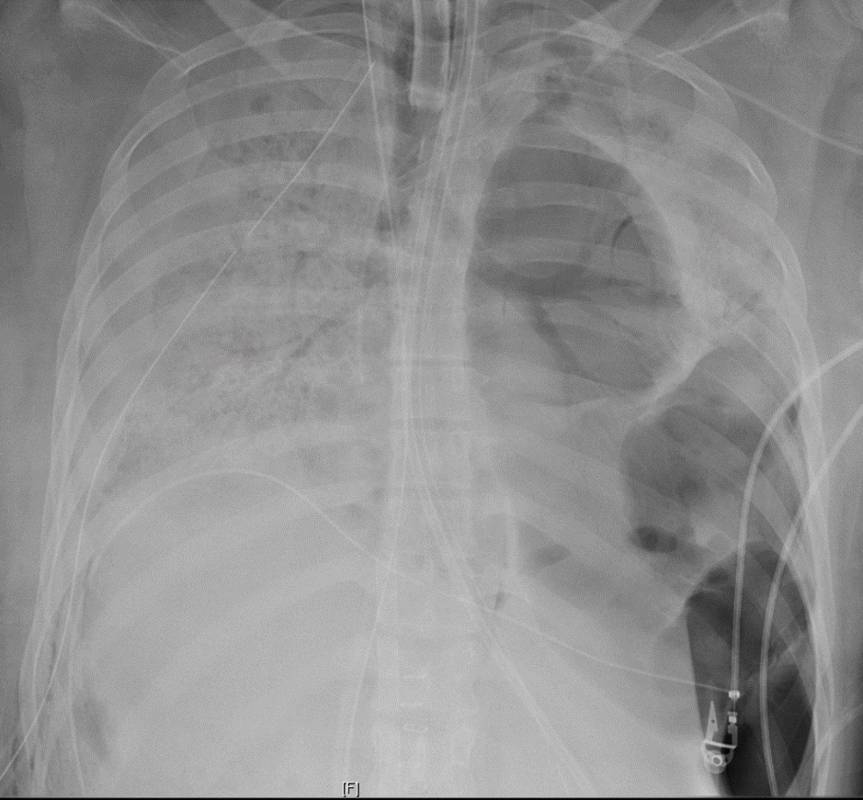

据外媒报道,在一名新冠肺炎患者肺部严重受损并只能靠呼吸机维持生命后,美国医生们首次对一名COVID-19患者进行了先进的肺移植手术。这场风险很大的手术是在美国西北纪念医院进行的,专家们得出结论,如果没有两个新肺,病人将没有生存的机会。

虽然围绕COVID-19的不确定性仍然存在,但病毒的某些方面及其对人体的影响已经非常清楚。新冠病毒会对肺部产生重大影响,特别是在感染的晚期阶段。这可能导致肺炎、急性呼吸窘迫综合征和败血症,造成持久的损害。

移植手术是在对于这个特殊的COVID病人(一位20多岁的西班牙裔女性)进入重症监护室六周后进行的。这涉及到由呼吸机和体外膜氧合(ECMO)的机器支持,有效地接管了她受损的心脏和肺部的工作。医院说,即使有这种支持,"到6月初,病人的肺部出现了不可逆的损伤"。

部分挑战在于,虽然如果这名女子要想存活下来,移植显然是必要的。“在许多天里,她是COVID ICU中也可能是整个医院里病得最重的人,”西北纪念医院的肺部和重症监护专家Beth Malsin说。“有这么多次,白天和晚上,我们的团队必须迅速做出反应,帮助她的氧合,并支持她的其他器官,以确保它们足够健康,以支持移植,如果和当机会到来。”

胸外科主任、外科主任Ankit Bharat医学博士将手术描述为“相当具有技术挑战性”。根据西北医学的数据,超过85%至90%的肺移植患者都能继续存活一年。尽管如此,仍有很多问题。虽然COVID-19患者的完整医疗记录尚未公布,但医院将她描述为“一个20多岁的健康女性”。“关于COVID-19,我们还有很多东西没有了解,”肺科医生、该医院肺移植项目的医学主任Rade Tomic博士承认。“例如为什么有些病例比其他病例病情更糟糕?”